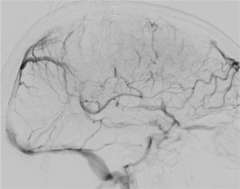

Figure 3

Anticoagulation, the administration of a blood thinning drug is the first line of treatment and has been shown to be very effective. However, when the clot burden is too large and/or the patient condition deteriorates despite anticoagulation treatment, catheter based clot-busting treatment becomes a consideration (Figure 3).